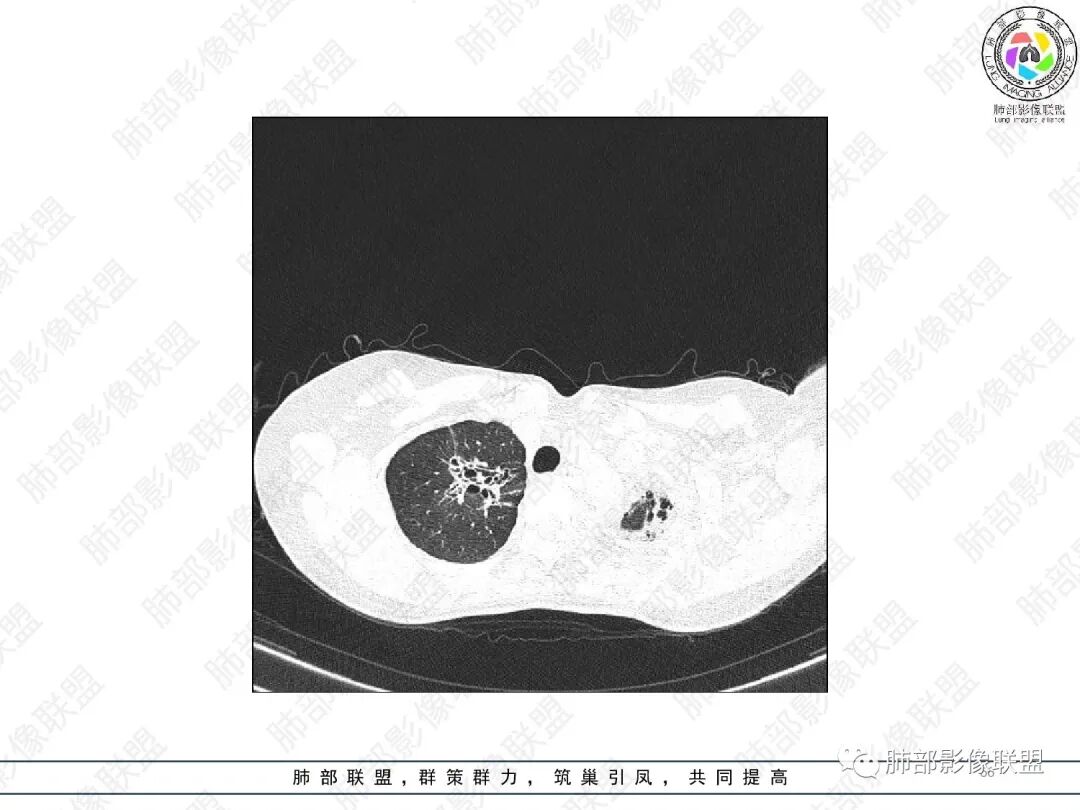

2.胸部CT:右肺上叶及中叶不规则块状影,沿支气管走行方向指套样影,支气阻塞湖嵌塞,腔内可见高密度影。灶周可见磨玻璃,外围见结节影及树芽征。左肺体积缩小,见不规则条索影、胸膜增厚,纵隔牵拉左移。

3.综合分析:结合患者病史及胸部CT主要鉴别ABPA(右肺上叶不规则块影,指套样顺延支气管方向,抗结核治疗1年,肺部病灶仍明显)及继发性肺结核TB(右肺上叶不规则肿块,其可见高密影,边缘模糊,周围卫星灶、树芽征,沿支气管爬行)。

胸部影像学的特异性改变:随着胸部高分辨率CT(HRCT)的普及,ABPA常见肺部影像表现包括黏液嵌塞、支气管扩张、小叶中心性结节、树芽征和马赛克征等。根据是否有中心性支气管扩张,ABPA可分为变态反应性支气管肺曲霉病-血清IgE增高型(ABPA-S)和变态反应性支气管肺曲霉病-中心性支气管扩张型(ABPA-CB)。气道黏液嵌塞在ABPA很常见,胸部HRCT上表现为指套征或牙膏征。气道黏液栓通常为低密度影,但20%也可为高密度黏液影(high-attenuation mucus,HAM),定义为气道内黏液栓密度高于脊柱旁肌肉的 HRCT值,这也成为ABPA特征性的影像表现之一,外周细支气管黏液阻塞可见“树芽征”。中央性支气管扩张曾一直是ABPA诊断标准之一,但其用于诊断ABPA的敏感度仅为37%。此外,33%~43%的中央性支气管扩张也可延伸至外周,26%~39%的ABPA只有周围性支气管扩张。因此,目前认为中央性支气管扩张应视为ABPA的并发症,而非其诊断标准。